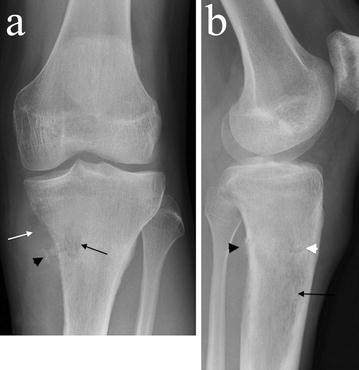

Plain radiographs demonstrated a poorly defined, permeative, radiolucent lesion, centred in the proximal tibial meta-diaphysis. A pathological fracture was present (Fig. 1).

a AP and lateral b plain radiographs demonstrate an ill-defined radiolucent lesion in the proximal tibial metadiaphysis (black arrows) with posteromedial cortical destruction and adjacent ossification (black arrowheads). A medial soft tissue mass with low density raises the possibility of a fatty matrix (white arrow). A pathological fracture is present (white arrowhead)

There was postero-medial cortical destruction with adjacent areas of ossification. There was evidence of low density in the medial soft tissue mass, raising the possibility of a fatty matrix.